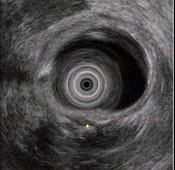

问题 男性,44岁反复上腹钝痛2年余伴纳差,超声内镜如图,胰腺病变可能的诊断是 ( )

选项 A.正常 B.胰腺囊肿 C.慢性胰腺炎 D.胰腺囊腺癌 E.胆总管结石伴扩张

答案 C